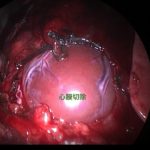

出血性心タンポナーデに対する胸腔鏡下心膜切除術

ゴールデンレトリバーは血管肉腫の好発犬種です。特に右心耳、肝臓、脾臓などに発生する事が知られています。右心耳であれば心タンポナーデという状態を引き起こし、循環状態が悪化し低血圧となり突然倒れてしまいます。聴診でマッフルサウンド、心電図では電気的交互脈、胸部エックス線ではムーンハートを呈しています。超音波で拡張期に右心房が虚脱する様子が確認されます。心嚢内圧を下げるために、直ちに心膜穿刺術で救命を行います。残念ながらこの腫瘍に対する根治的な治療方法はなく、進行すれば再発性の出血性心タンポナーデを何度も繰り返す(何度も倒れる)ことになります。そこで、姑息的な手段ですが心膜切除術を行なっておけば心タンポナーデを回避する事が出来ます。近年、テクノロジーの発展とともに開胸術ではなく胸腔鏡を使って小さな傷で手術を行う事が可能となっています。この病気は突然ワンコを襲い、見つかった時はすでに進行している事がほとんどです。だからこそ、最小侵襲で最大の効果が期待できる胸腔鏡下心膜切除術に真の価値があると言えます。開胸術に比べ痛みも少なく入院も短くて済むからです。我々はたとえ根治不能な病気であっても、患者さんがQOLを保ちながらご家族との大切な時間を1日でも長く過ごせるように、チームで話し合いながら”より良い”を常に模索し続けます。